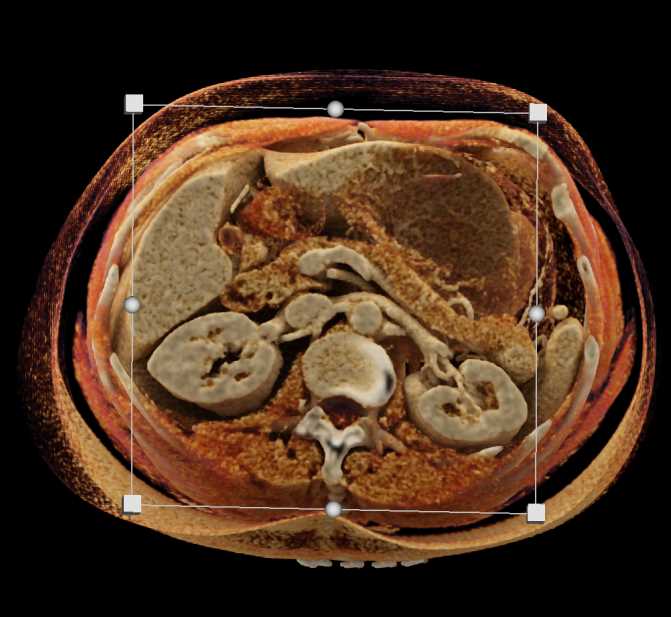

Gaucher's Spleen